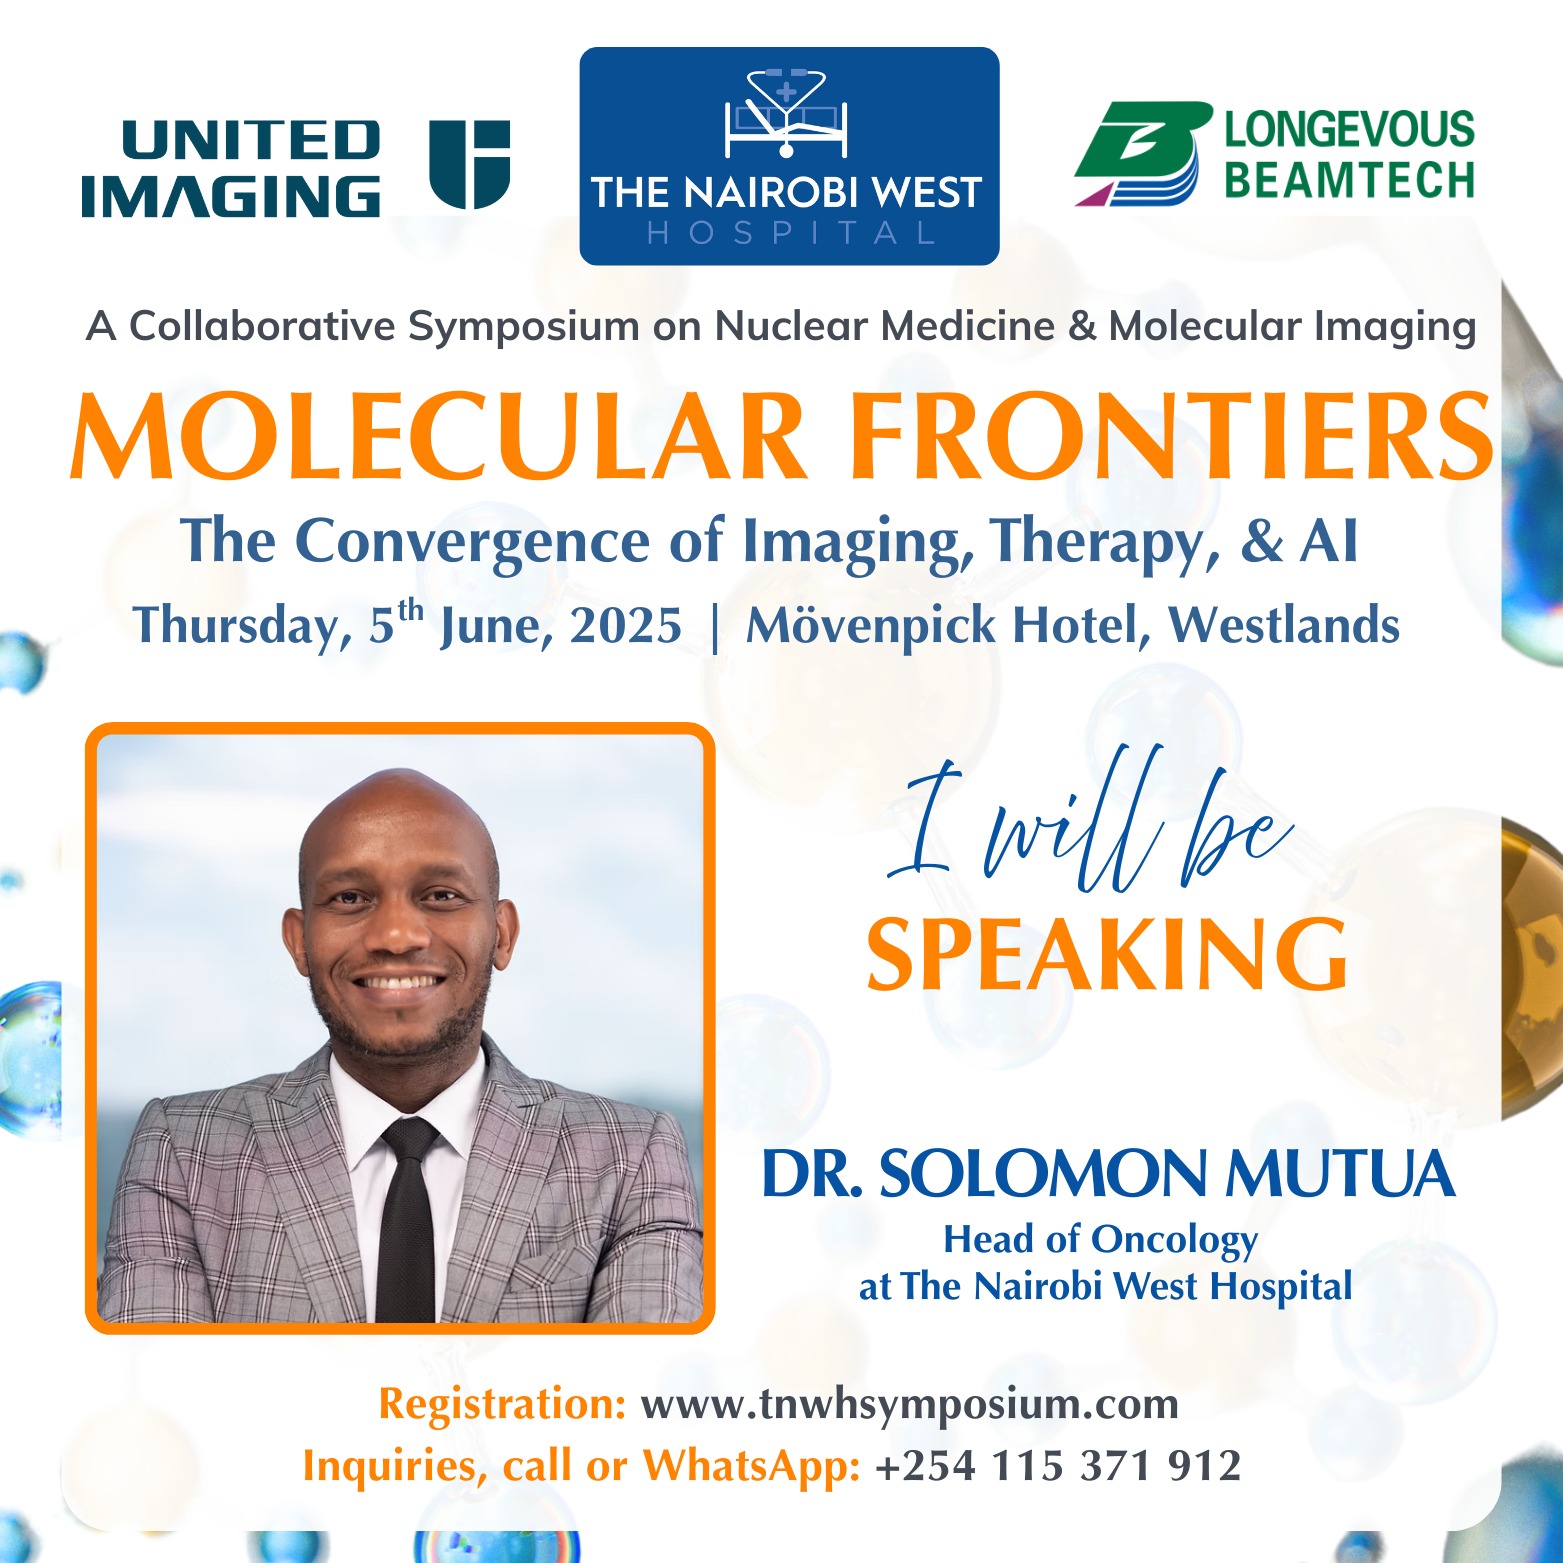

Molecular Frontiers

Don't miss this collaborative symposium hosted by The Nairobi West Hospital, United Imaging Healthcare, and Longevous Beamtech at Movenpick Hotel, Nairobi.

Discover the latest advancements in nuclear medicine, molecular imaging, therapy, AI, and patient care through insightful presentations and engaging panel discussions.

Early-bird ends 25th May 2025

Date: June 5, 2025

Dr. Solomon Mutua - Consultant Clinical Oncologist

MBChB (UoN), MMed (UKZN), FC Rad Onc (CMSA)

Dr. Solomon Mutua is a Clinical Oncologist who specialises in Medical and Radiation Oncology. He is based at The Nairobi West Hospital in Kenya, where he leads the oncology department.

Dr. Mutua holds medical degrees from the University of Nairobi and the University of KwaZulu-Natal, along with a Fellowship in Radiation Oncology from the Colleges of Medicine of South Africa.

He has extensive experience in advanced radiotherapy techniques such as IMRT (Intensity-Modulated Radiation Therapy), VMAT (Volumetric Modulated Arc Therapy), IGRT (Image-Guided Radiation Therapy), TBI (Total Body Irradiation), SRS (Stereotactic Radiosurgery), and Brachytherapy.

Additionally, he is skilled in radiopharmaceutical therapies, including I-131, Lutetium-177, and Y-90 SIRT (Selective Internal Radiation Therapy), as well as systemic cancer treatments like chemotherapy, targeted therapy, hormonal agents, and immunotherapy.

Dr. Mutua is recognized for his patient-centered and compassionate approach, particularly in counseling and communication, which makes him a trusted leader in the field of cancer care.